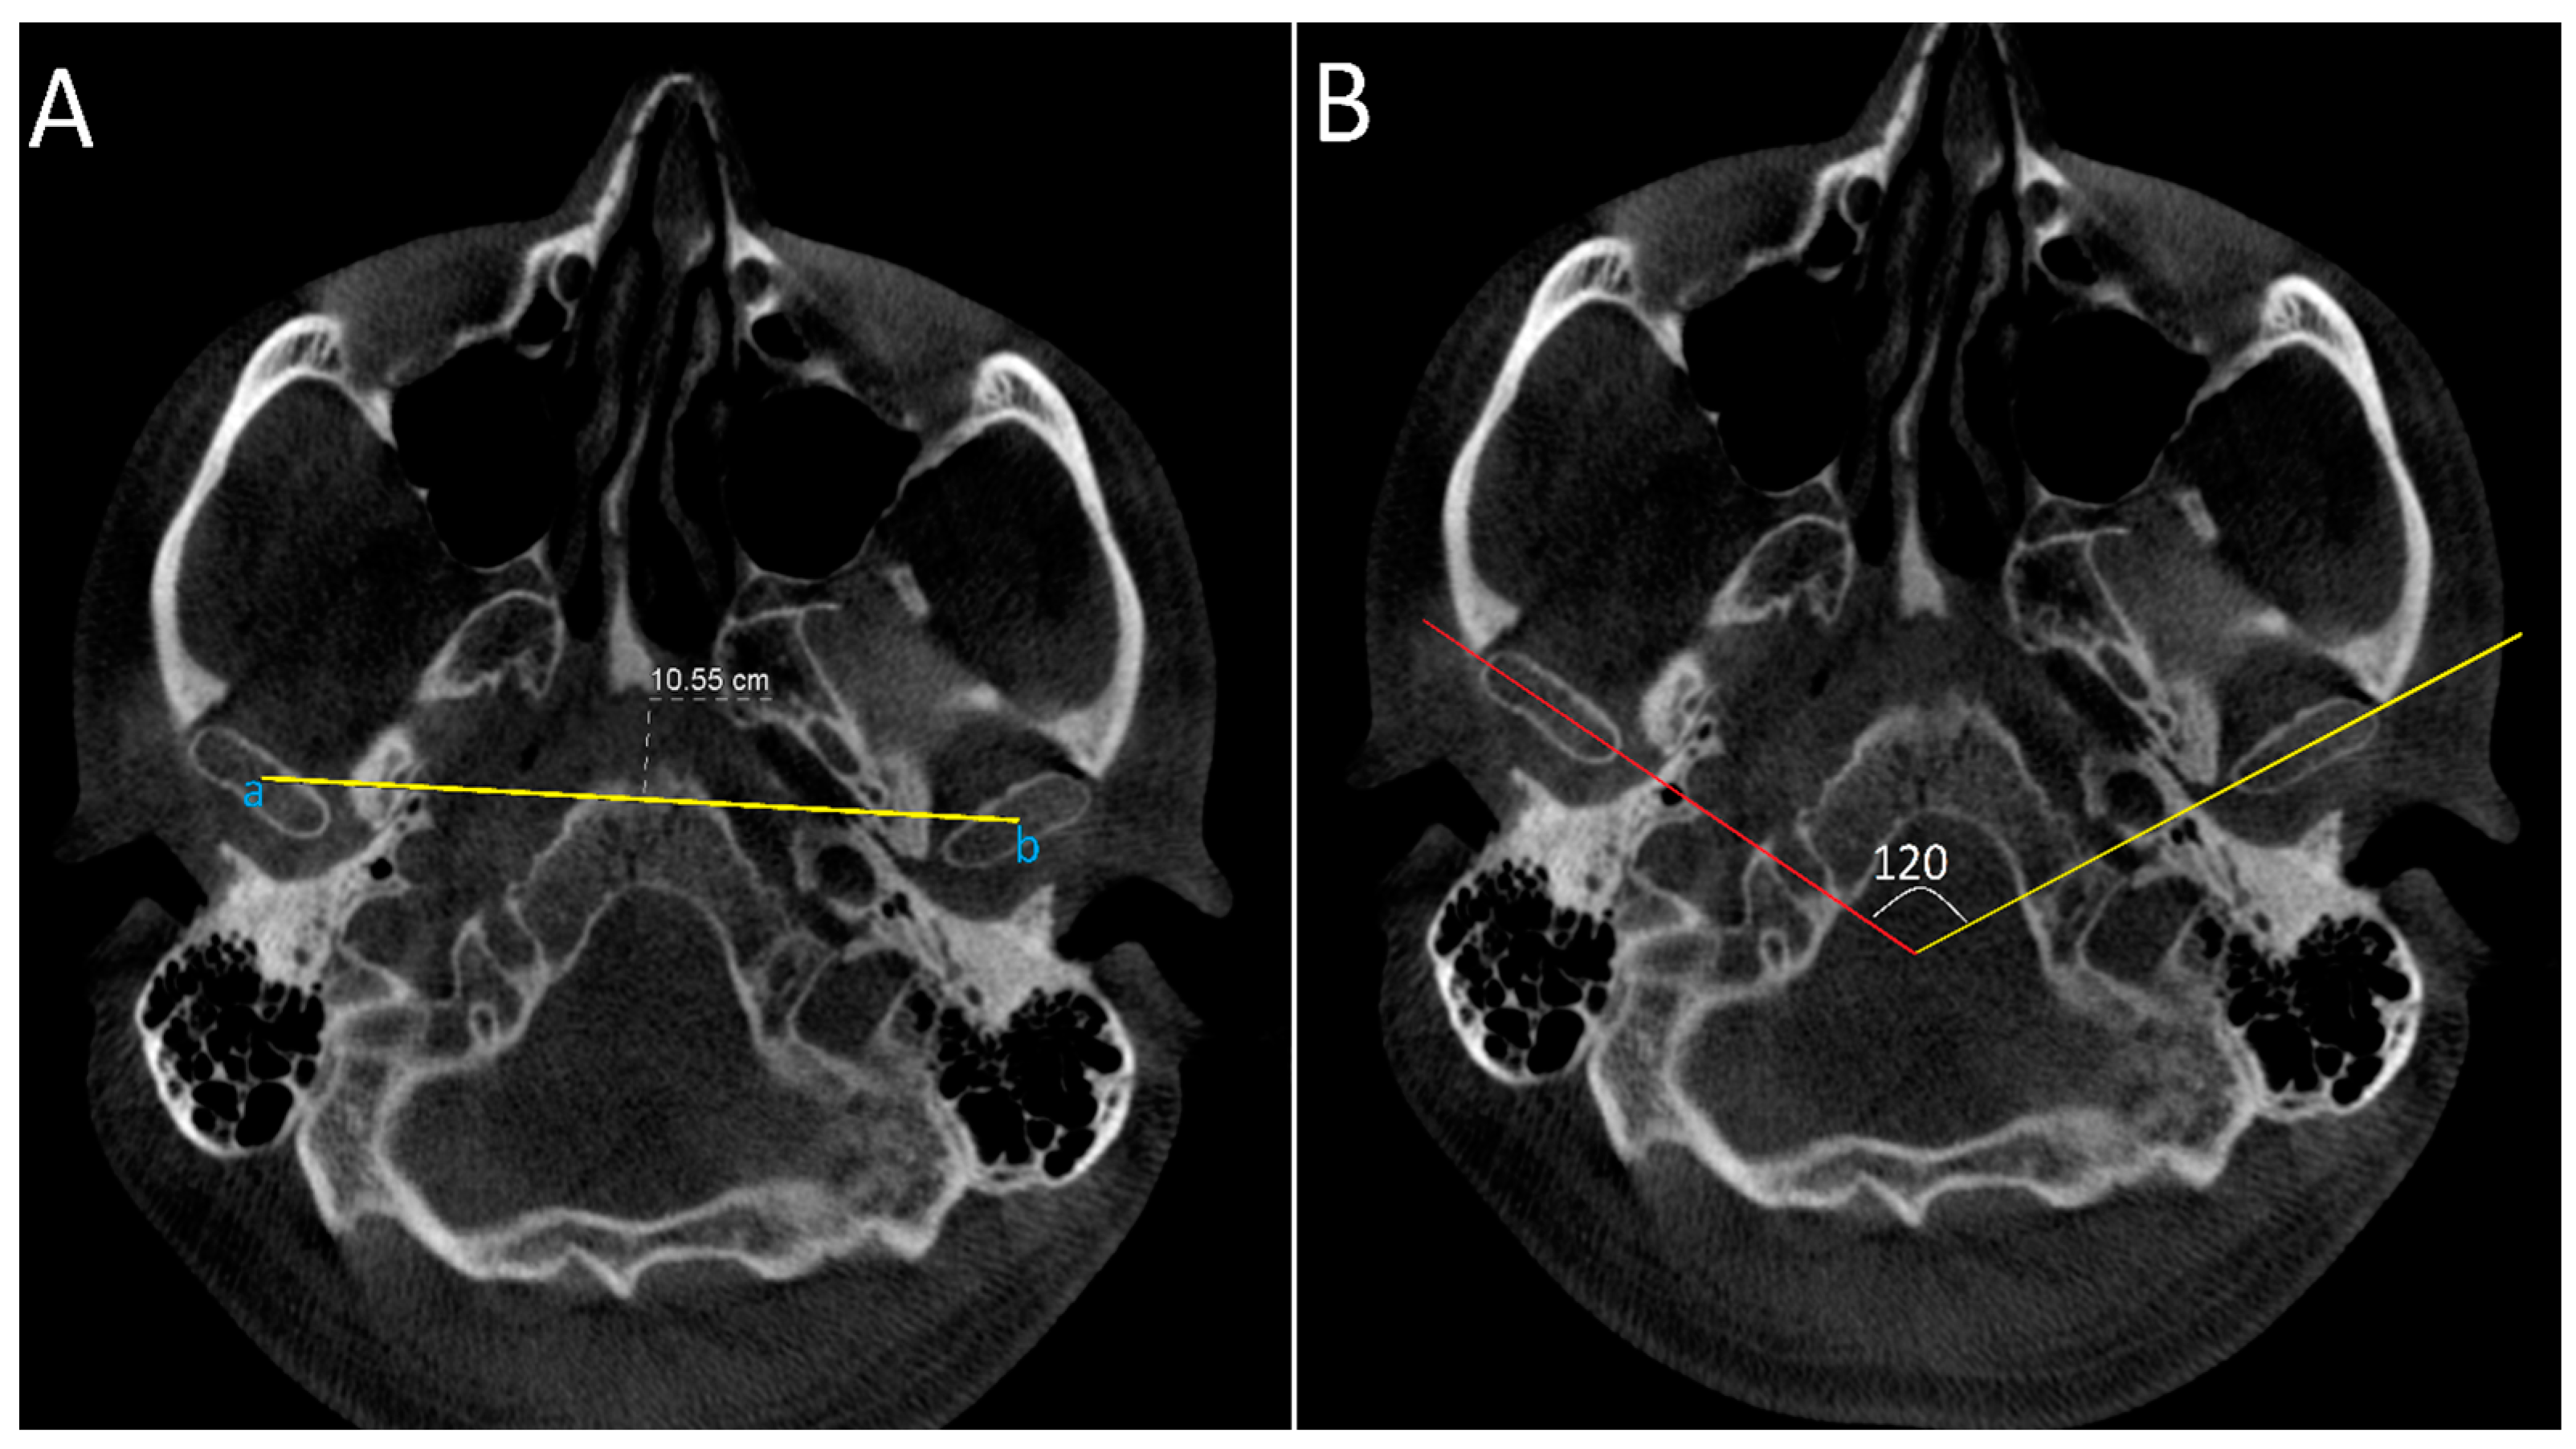

2.4.1. Axial Projection: Measurements Were Conducted on the Slice with the Largest Condylar Dimensions in the Axial Plane (Figure 2)

- Intercondylar distance: defined as the distance between midpoint of right and left condylar heads.

- Intercondylar angle: defined as the angle formed between lines connecting medial and lateral poles of the condylar heads on both sides.